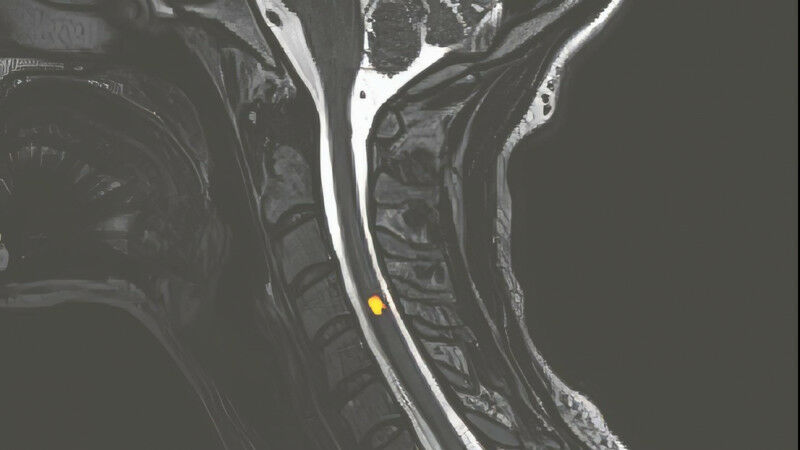

Ärzte sind in der Lage, einen gebrochenen Knochen zu identifizieren, einen Tumor zu erkennen oder ein Baby im Mutterleib zu beobachten - und das alles auf eine für die Patienten nicht invasive Weise. Wie weit können wir in den menschlichen Körper hineinschauen? Der Bereich der medizinischen Bildgebung entwickelt sich ständig weiter, um immer genauere Bilder zu erhalten und kleinere Anomalien zu erkennen. Professor Dimitri Van De Ville sieht zwei Trends in der Magnetresonanztomographie (MRT). "Ein erster Forschungsbereich entwickelt Maschinen mit einem stärkeren Magnetfeld, um kleinere Anomalien wie Mikroverletzungen oder Krebszellen in einem frühen Entwicklungsstadium zu erkennen", erklärt der Leiter des Labors für medizinische Bildverarbeitung an der EPFL.

Die gängigsten MRT-Geräte in Krankenhäusern verfügen über ein Magnetfeld von 1,5 oder 3 Tesla. Wissenschaftler des Commissariat à l’énergie atomique et aux énergies alternatives in der Nähe von Paris haben dagegen das weltweit stärkste Gerät entwickelt, bei dem das Magnetfeld 11,7 Tesla erreicht.

Auf Seiten der EPFL arbeiten die Wissenschaftler mit einer eigenen Maschine, die sich im Centre d’imagerie biomédicale (CIBM) befindet und 7 Tesla anzeigt. Diese Art von Hochleistungsmaschine ermöglicht es, menschliche Gehirne in vivo nach neuronalen Schichten zu kartografieren. "Friedhelm Hummel, Professor und Inhaber des Defitech-Lehrstuhls für klinische Neuroengineering-Forschung und Mensch-Maschine-Interaktion am Neuro-X-Institut, erklärt: "Auf diese Weise können wir die Strukturen des Gehirns besser verstehen, denn bis heute ist nicht klar, was sie wirklich darstellen.

Der zweite Trend besteht darin, das Magnetfeld auf deutlich unter 1,5 Tesla zu reduzieren, ohne den Informationsgehalt des Diagnosebildes zu beeinträchtigen, um billigere Geräte herzustellen, die leichter zu transportieren und zu installieren sind, insbesondere in Entwicklungsländern. "Dies wird durch Fortschritte in der Technologie ermöglicht, wie z. B. bei Sensoren, Geräten oder der Datenverarbeitung, die zum Teil an der EPFL stattfinden", erklärt Dimitri Van De Ville.

Je höher wir im Magnetfeld aufsteigen, desto feinere und subtilere Informationssignale messen wir.

Jean-Philippe Thiran, Professor und Direktor des Labors für Signalverarbeitung